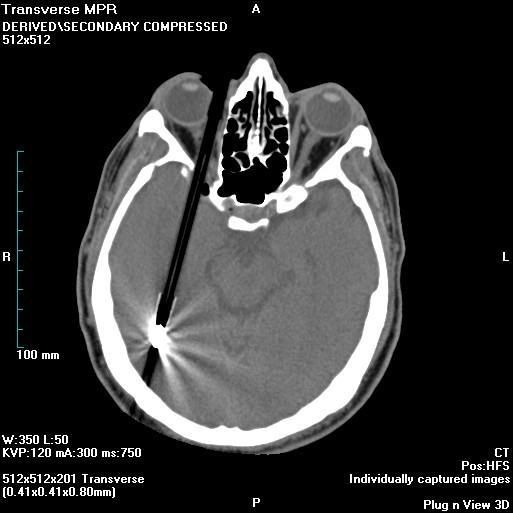

Credit: Dr Laughlin Dawes

"This patient presented with a self-harm injury. The axial CT scan shows a ball-point pen in-situ. The pen missed optic nerve, middle cerebral artery and any eloquent brain. A cerebral angiogram was performed which was normal except for truncation of the ophthalmic artery. The pen was removed under flouroscopic guidance. Upon removal, there was brisk bleeding from the ophthalmic artery. Endovascular embolisation of the bleeding vessel was performed with coils, with good result. The patient’s pupil remains reactive, suggesting a good prognosis for the optic nerve and the patient’s vision. "